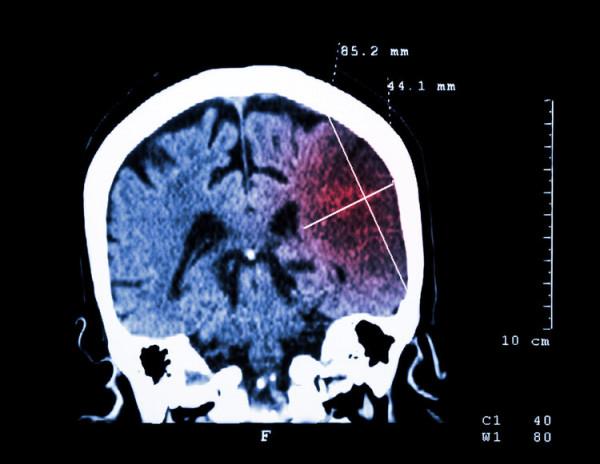

次日,縣醫院給王姥姥進行了頭顱CT檢查,提示腦幹出血,住院搶救48小時無效死亡。